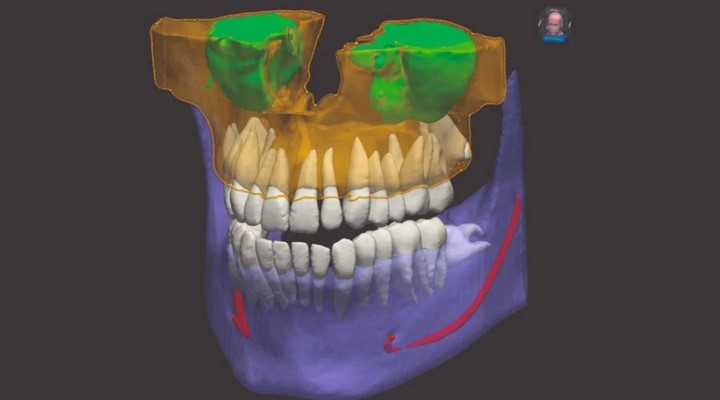

Neowise gives you a complete view of each patient’s diagnostic journey, from X-rays and CBCT scans to 3D renders and treatment simulations, all in one place. Everything is securely stored and instantly accessible through a single, intuitive dashboard.

Using patented AI tools, it automatically identifies anatomical structures, traces nerves, segments images, and highlights potential issues in both panoramic and intraoral views.